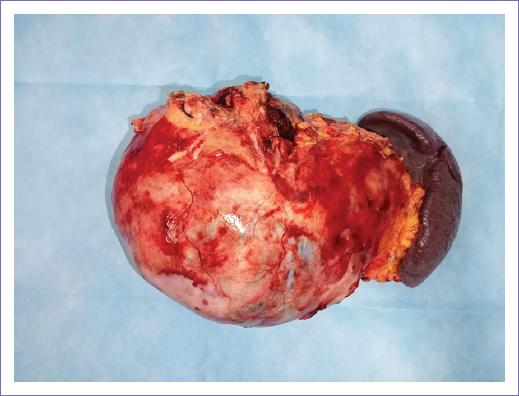

Surgery 09/25/2021: The procedure was performed with mixed epidural anesthesia in addition to balanced general anesthesia, requiring low-dose vasopressor (norepinephrine) during the procedure. Distal pancreatectomy and open splenectomy were performed, finding a lobulated cystic tumor of the pancreas measuring 25 × 30 cm, adhered to the transverse colon and posterior wall of the stomach, bleeding during surgery: 800 cc, with no complications reported (Fig. 2).

Figure 2 Surgical piece result from distal pancreatectomy and open splenectomy: lobulated cystic tumor of the pancreas measuring 25 × 30 cm.

Despite there was no evidence of cancer, the surgical approach was to get R0 or resect all the lesion. Surgical findings revealed a lobulated cystic tumor measuring approximately 25 × 30 cm. It was firmly adherent to the transverse colon, posterior stomach wall, splenic vessels, superior mesenteric vein, and portal vein. The surgery was performed through a supra-infraumbilical midline incision. The posterior aspect of the pancreatic neck was dissected and transected using a stapler. The tumor capsule was dissected from the adhered organs using a harmonic scalpel, and a splenectomy was performed. The surgery was classified as a distal pancreatectomy with splenectomy.